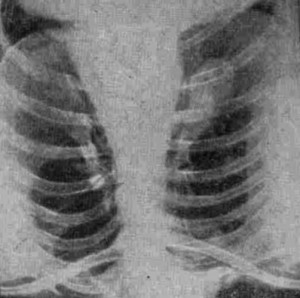

Płuca palacza

/ Fot.